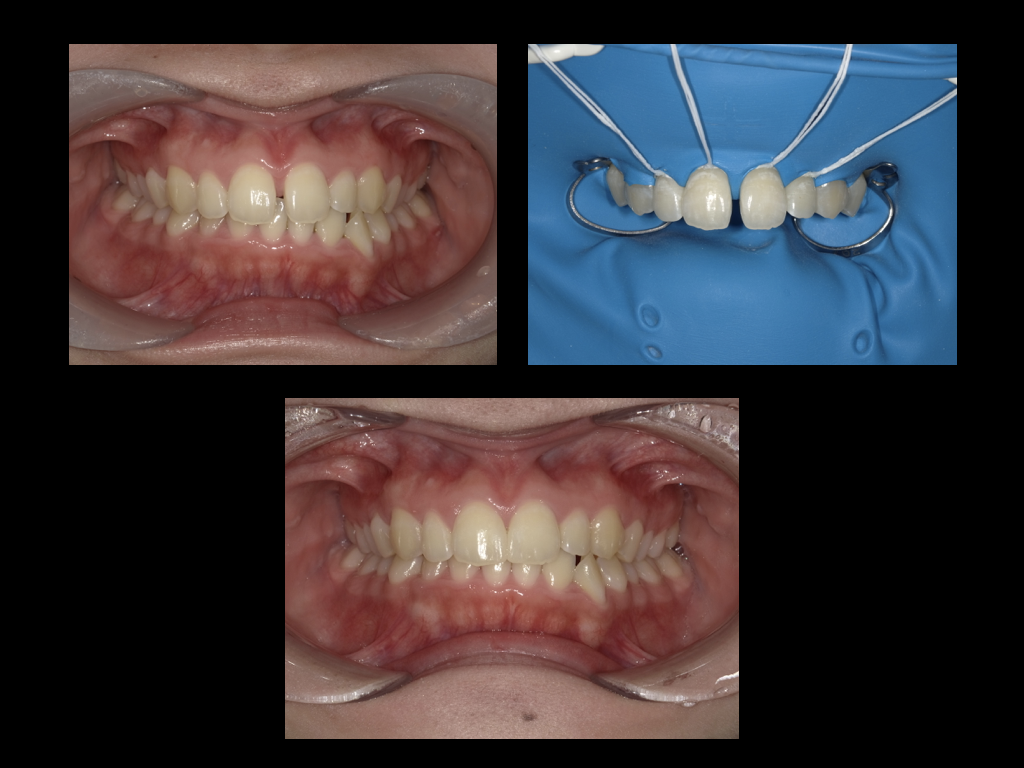

高い審美性を誇るダイレクトボンディング治療

当院では最新の歯科材料を使い、より審美性に優れたダイレクトボンディング治療をご提供しております。

当院では最新の歯科材料を使い、より審美性に優れたダイレクトボンディング治療をご提供しております。

ダイレクトボンディング専門で出張もしており症例も豊富です。

透明性の高い医療をご提供するためにも、術前・術後の写真をお見せしたりと、患者様が知りたいと思う情報を全て開示しています。

ダイレクトボンディング イメージ

ラバーダム防湿による治療

ラバーダムとは、治療する歯以外の場所をカバーする「ゴム製のシート」のことです。

ダイレクトボンディングに使用する接着剤や詰め物は、水分があると最大限の力を発揮できません。

お口は唾液や呼気など湿気が多いため、ラバーダムを使用することによりお口の中の湿気を排除することができ、より精度・耐久性のよい詰め物となります。